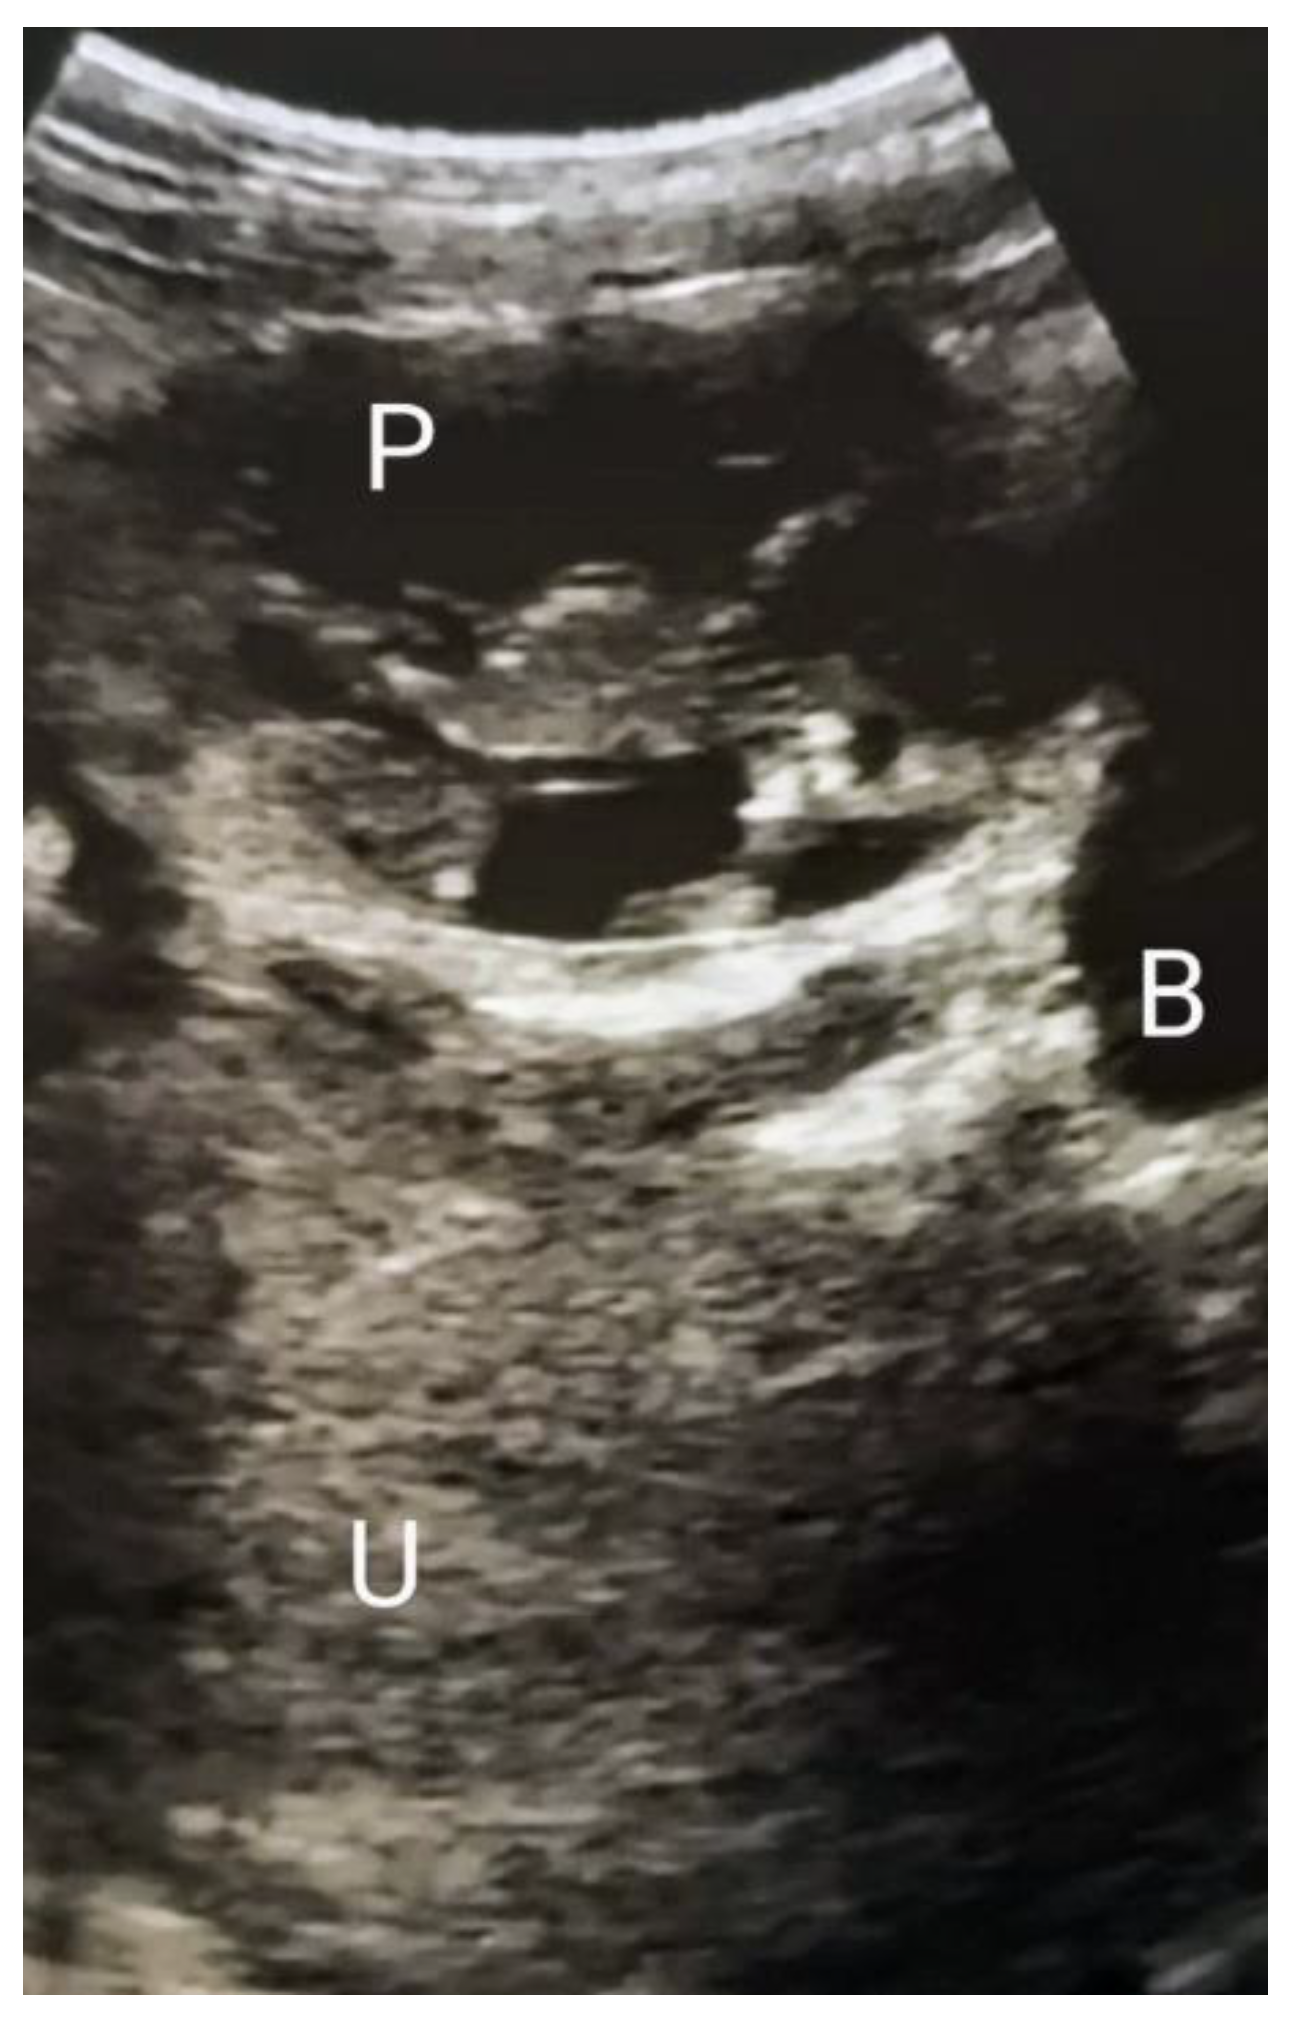

Figure 1.

First trimester abdominal ultrasound scan showing the abdominal pregnancy, the empty uterus, and the absence of free fluid in the abdomino–pelvic cavity. P = pregnancy; U = uterus; B = bladder.

A 26-year-old gravida 2 para 0, was referred to Princess Christian Maternity Hospital, Freetown, Sierra Leone, with amenorrhea of three months duration a three day history of worsening pelvic pain. She had a prior history of right salpingectomy performed 3 years before presentation as a result of ruptured right tubal EP. On examination, there was moderate tachycardia and lower abdominal tenderness; the pregnancy test was positive, and the transabdominal ultrasound scan revealed a 12-weeks left adnexal EP with a vital fetus and no free fluid collection in the pouch of Douglas (Figure 1). In this public academic hospital No other hematological diagnostic or imaging investigations were available, and they were not included in the free healthcare guaranteed by the national program. Blood tests and magnetic resonance imaging are carried out in other private institutions. A rapid test for hemoglobin was performed and the result was within the normal range. In the presence of the husband, the patient was offered detailed counselling for the management of her condition. Considering the vital fetus, the global consensus indicates the surgical removal of the pregnancy. As a symptom, pain could indicate impending or initial tubal rupture, and the consequent bleeding potentially threatens the patient’s survival. Therefore, emergency exploratory laparotomy was proposed for suspicion of the imminent rupture of the EP.